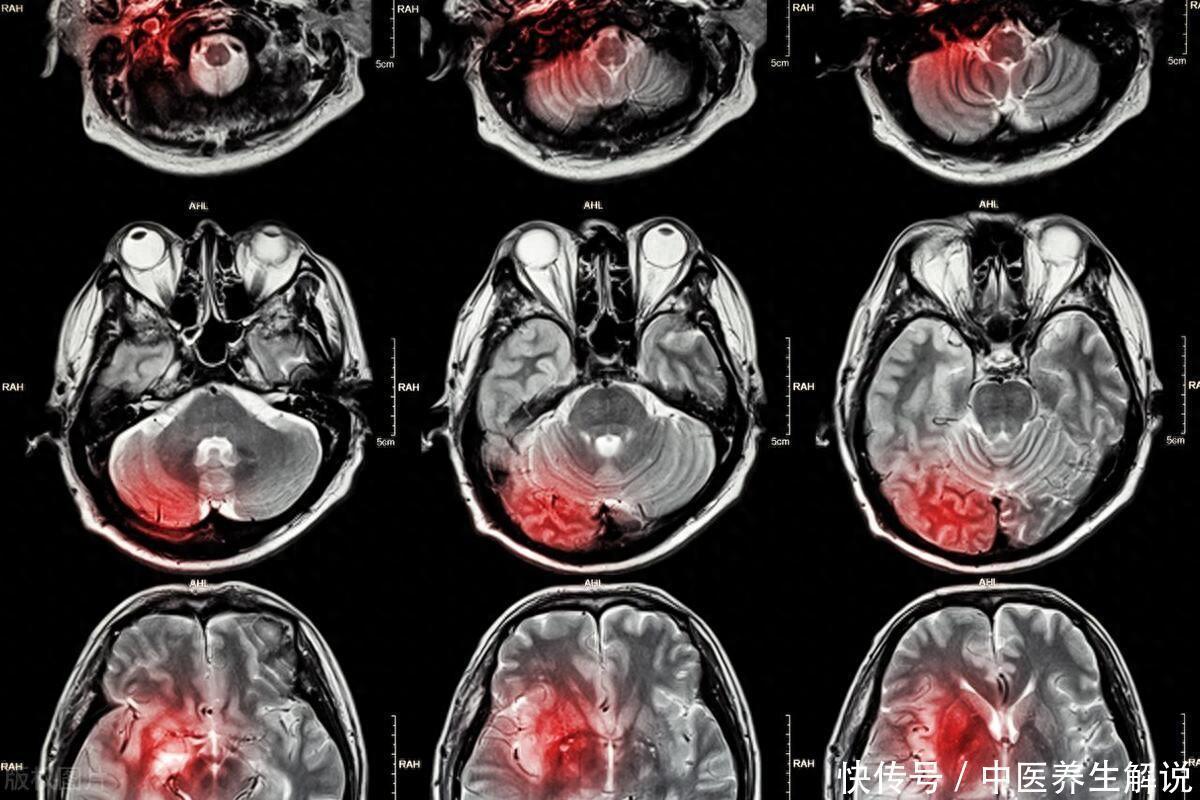

晨起爱抽烟的人,若出现这4个表现,可能是脑梗来临的信号!